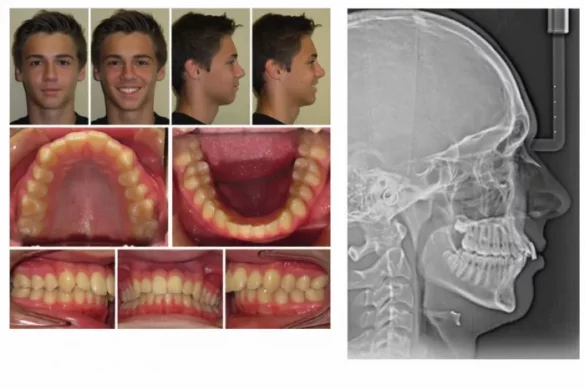

Skeletal Class III malocclusion refers to a situation in which the decrease jaw (mandible) is placed extra ahead than the higher jaw (maxilla). This disparity can end result from a distinguished or overgrown decrease jaw, an underdeveloped higher jaw, or a aggregate of each. Patients commonly showcase a poor overjet, in which the decrease the front enamel increase in the front of the higher enamel. This situation can purpose chunk problems, speech difficulties, and facial asymmetries.

For slight to mild instances or in sufferers who can’t go through surgical operation, orthodontists might also additionally choose camouflage techniques. Camouflage orthodontic remedy makes use of braces and elastics to transport enamel in a manner that mask the underlying jaw discrepancy. Dental reimbursement is frequently accomplished through retracting the decrease the front enamel and protracting the higher the front enamel. While this approach can enhance chunk and aesthetics, it can’t clear up skeletal issues. Sometimes, the dental reimbursement might also additionally have limitations, specially in excessive instances.

Each case of Class III malocclusion have to be evaluated on its very own merits. The severity of the skeletal discrepancy, the age and ordinary fitness of the affected person, and the affected person’s desires and expectancies all play roles in choosing a remedy plan. Diagnostic equipment consisting of cephalometric analysis, 3-D imaging, and thorough medical exam are crucial for expertise the underlying hassle and predicting remedy outcomes.